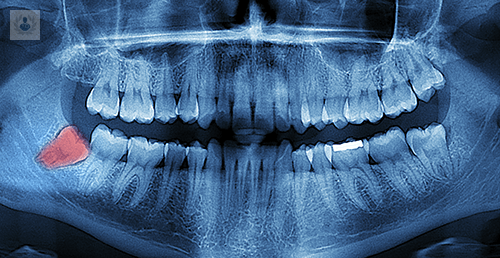

Cirugía de Extracción de los Cordales ¿En qué consiste?

La Extracción de las Cordales es una cirugía que se encarga de realizar la exodoncia de los terceros morales, ya sea que estos estén incluidos o parcialmente incluidos

¿Qué es la Extracción de Cordales? Conoce el procedimiento

La Extracción de Cordales, es la cirugía que se encarga de realizar la Exodoncia de los terceros morales incluidos o parcialmente incluidos.